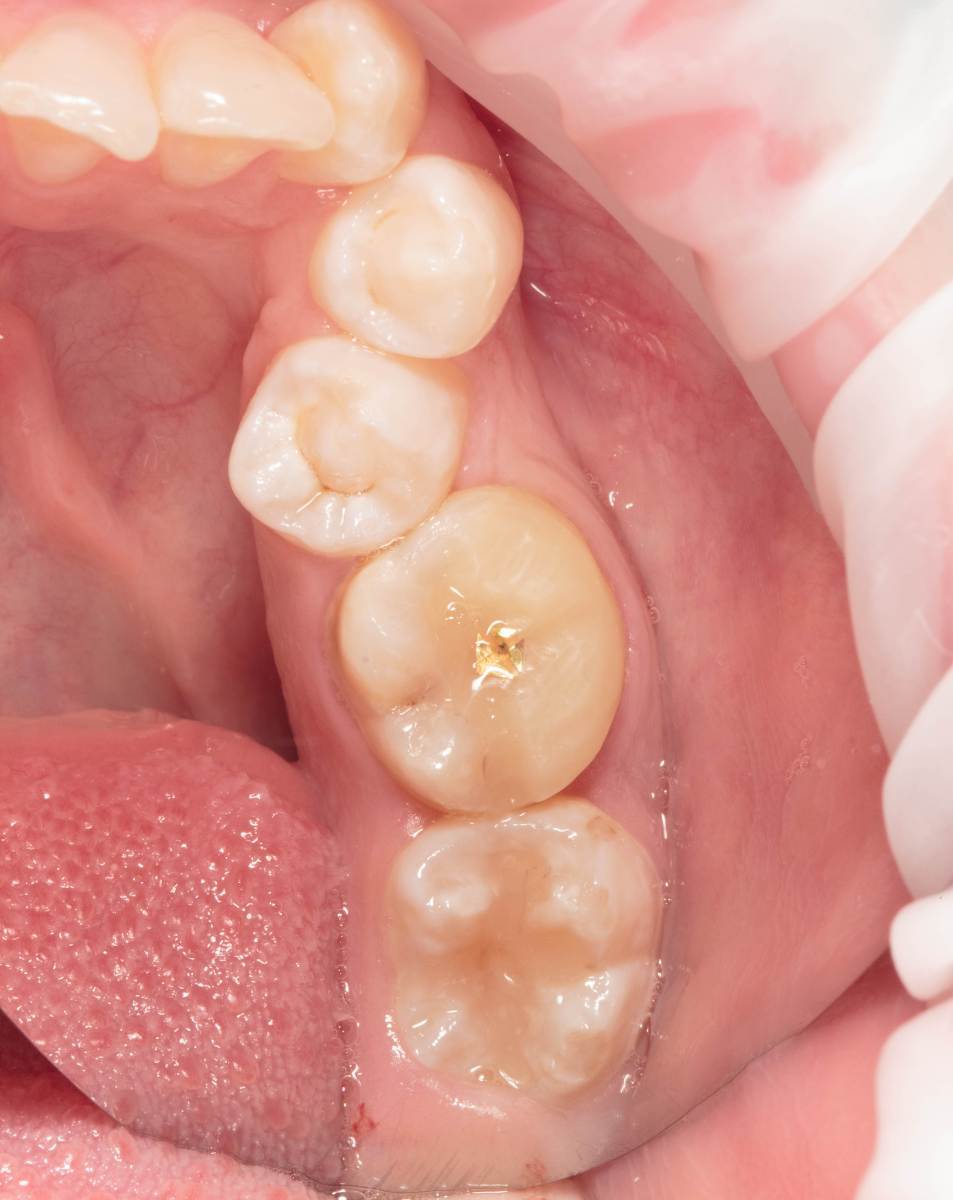

Женька Опубликовано 28 ноября, 2025 Поделиться Опубликовано 28 ноября, 2025 Всем привет, коллеги! 14 лет, терапевты ставят трещину по КТ (снимков до, к сожалению нет, косяк, каюсь). чуть сепарировав зуб и глянув на зуб под отлетевшим куском пломбы трещина "подтвердилась". Кейс на фото. Из интересного - маленький реколл в 1.5 года и спокойное перемещение зуба брекетами! 4 1 2 Ссылка на комментарий

Женька Опубликовано 17 декабря, 2025 Автор Поделиться Опубликовано 17 декабря, 2025 @сирена вот и завтра наступило) прощу прощения, что так долго, всё из головы вылетало на работе посмотреть. Пересадили в конце мая, к ортодонтии подключили в начале сентября ~3.5 месяца прошло с пересадки на тот момент. 1 Ссылка на комментарий